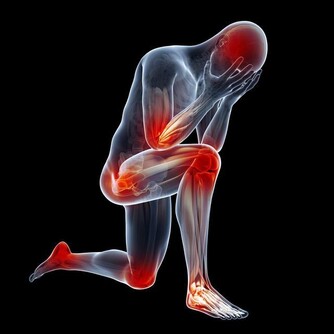

另外,患者也可能存在身體方面的問題,比如運動緩慢或身體僵硬,膀胱或腸道控制喪失(通常在晚期出現),肌肉無力或吞嚥困難。